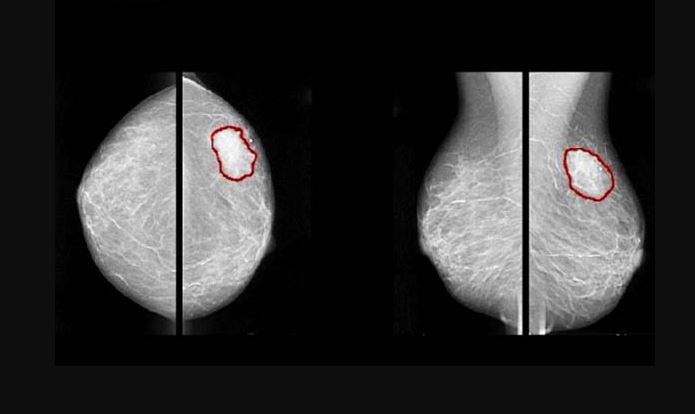

Mammografia to metoda badania piersi pozwalająca na wykrycie zmian nowotworowych piersi nawet na wczesnym etapie choroby, gdy możliwa jest jej skuteczne leczenie. Jest to metoda radiologiczna, która polega na wykonaniu serii zdjęć sutka przy użyciu promieni rentgenowskich.